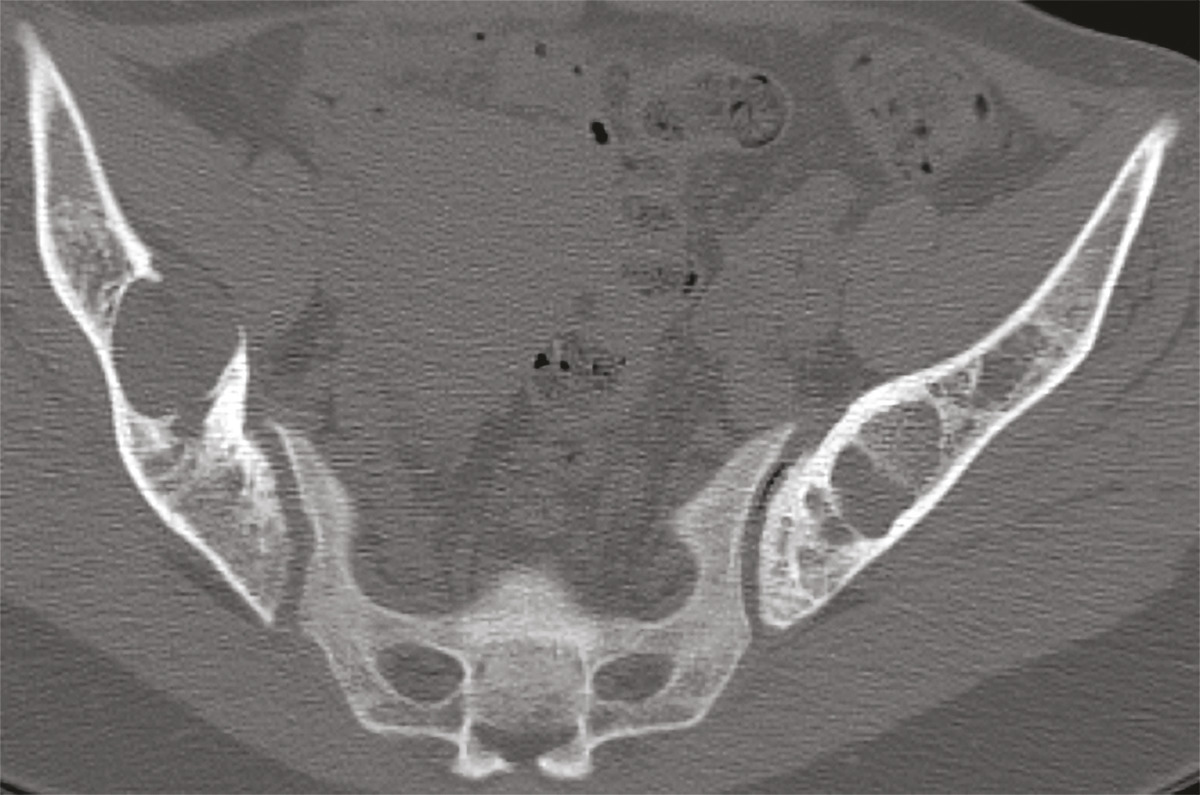

Cette femme de 31 ans sans antécédents était adressée pour des douleurs pelviennes, un syndrome polyuro-polydipsique et une altération de l’état général. Le bilan biologique montrait une hypercalcémie, une hypophosphorémie, une hypovitaminose D et une hyperparathormonémie. La tomodensitométrie (TDM) [fig. 1 ] et l’imagerie par résonance magnétique (IRM) [fig. 2 ] du pelvis révélaient un aspect ostéolytique diffus avec des nodules tumoraux des ailes iliaques. La scintigraphie et l’examen histologique de trois volumineuses glandes parathyroïdes permettait de retenir le diagnostic d’hyperplasie parathyroïdienne primaire. La biopsie osseuse confirmait le diagnostic de tumeurs brunes osseuses associées à l’hyperparathyroïdie. L’évolution était favorable sous traitement symptomatique et antalgique.

Ces tumeurs sont devenues rares du fait d’un diagnostic plus précoce de l’hyperparathyroïdie. Leur aspect radiologique est celui d’une ostéolyse non spécifique.2 Les principaux diagnostics différentiels sont les métastases osseuses et les lésions myélomateuses.